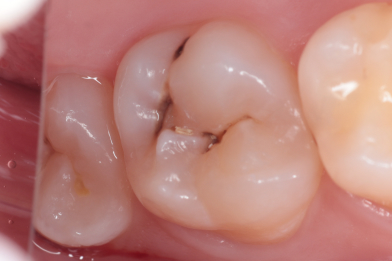

Лечение среднего кариеса 2.6. Функциональная и эстетическая реставрация зуба

Эвинян Лусине Артоевна -